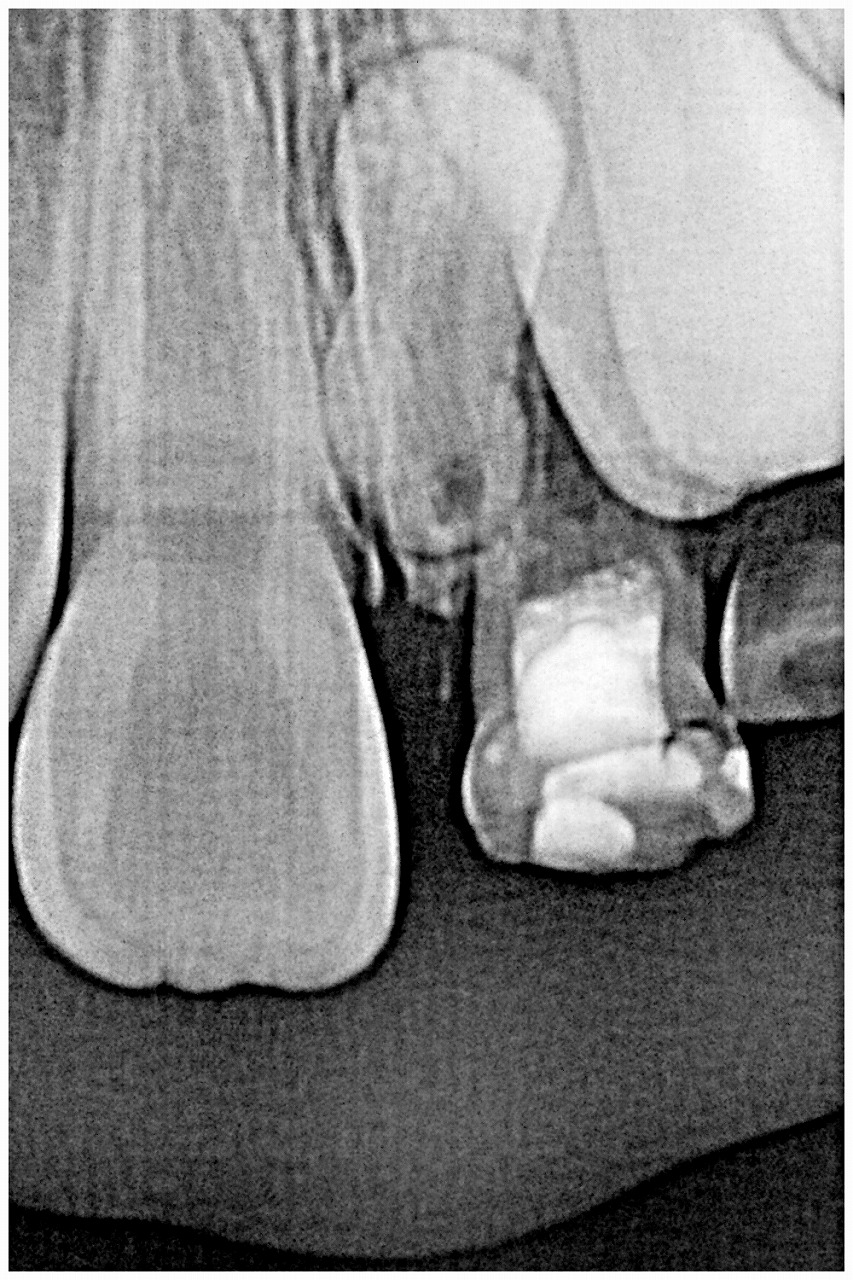

術前の状態になります

乳歯が2本確かに不自然

逆性の過剰歯が原因となっていました

ctにても骨内に存在していました